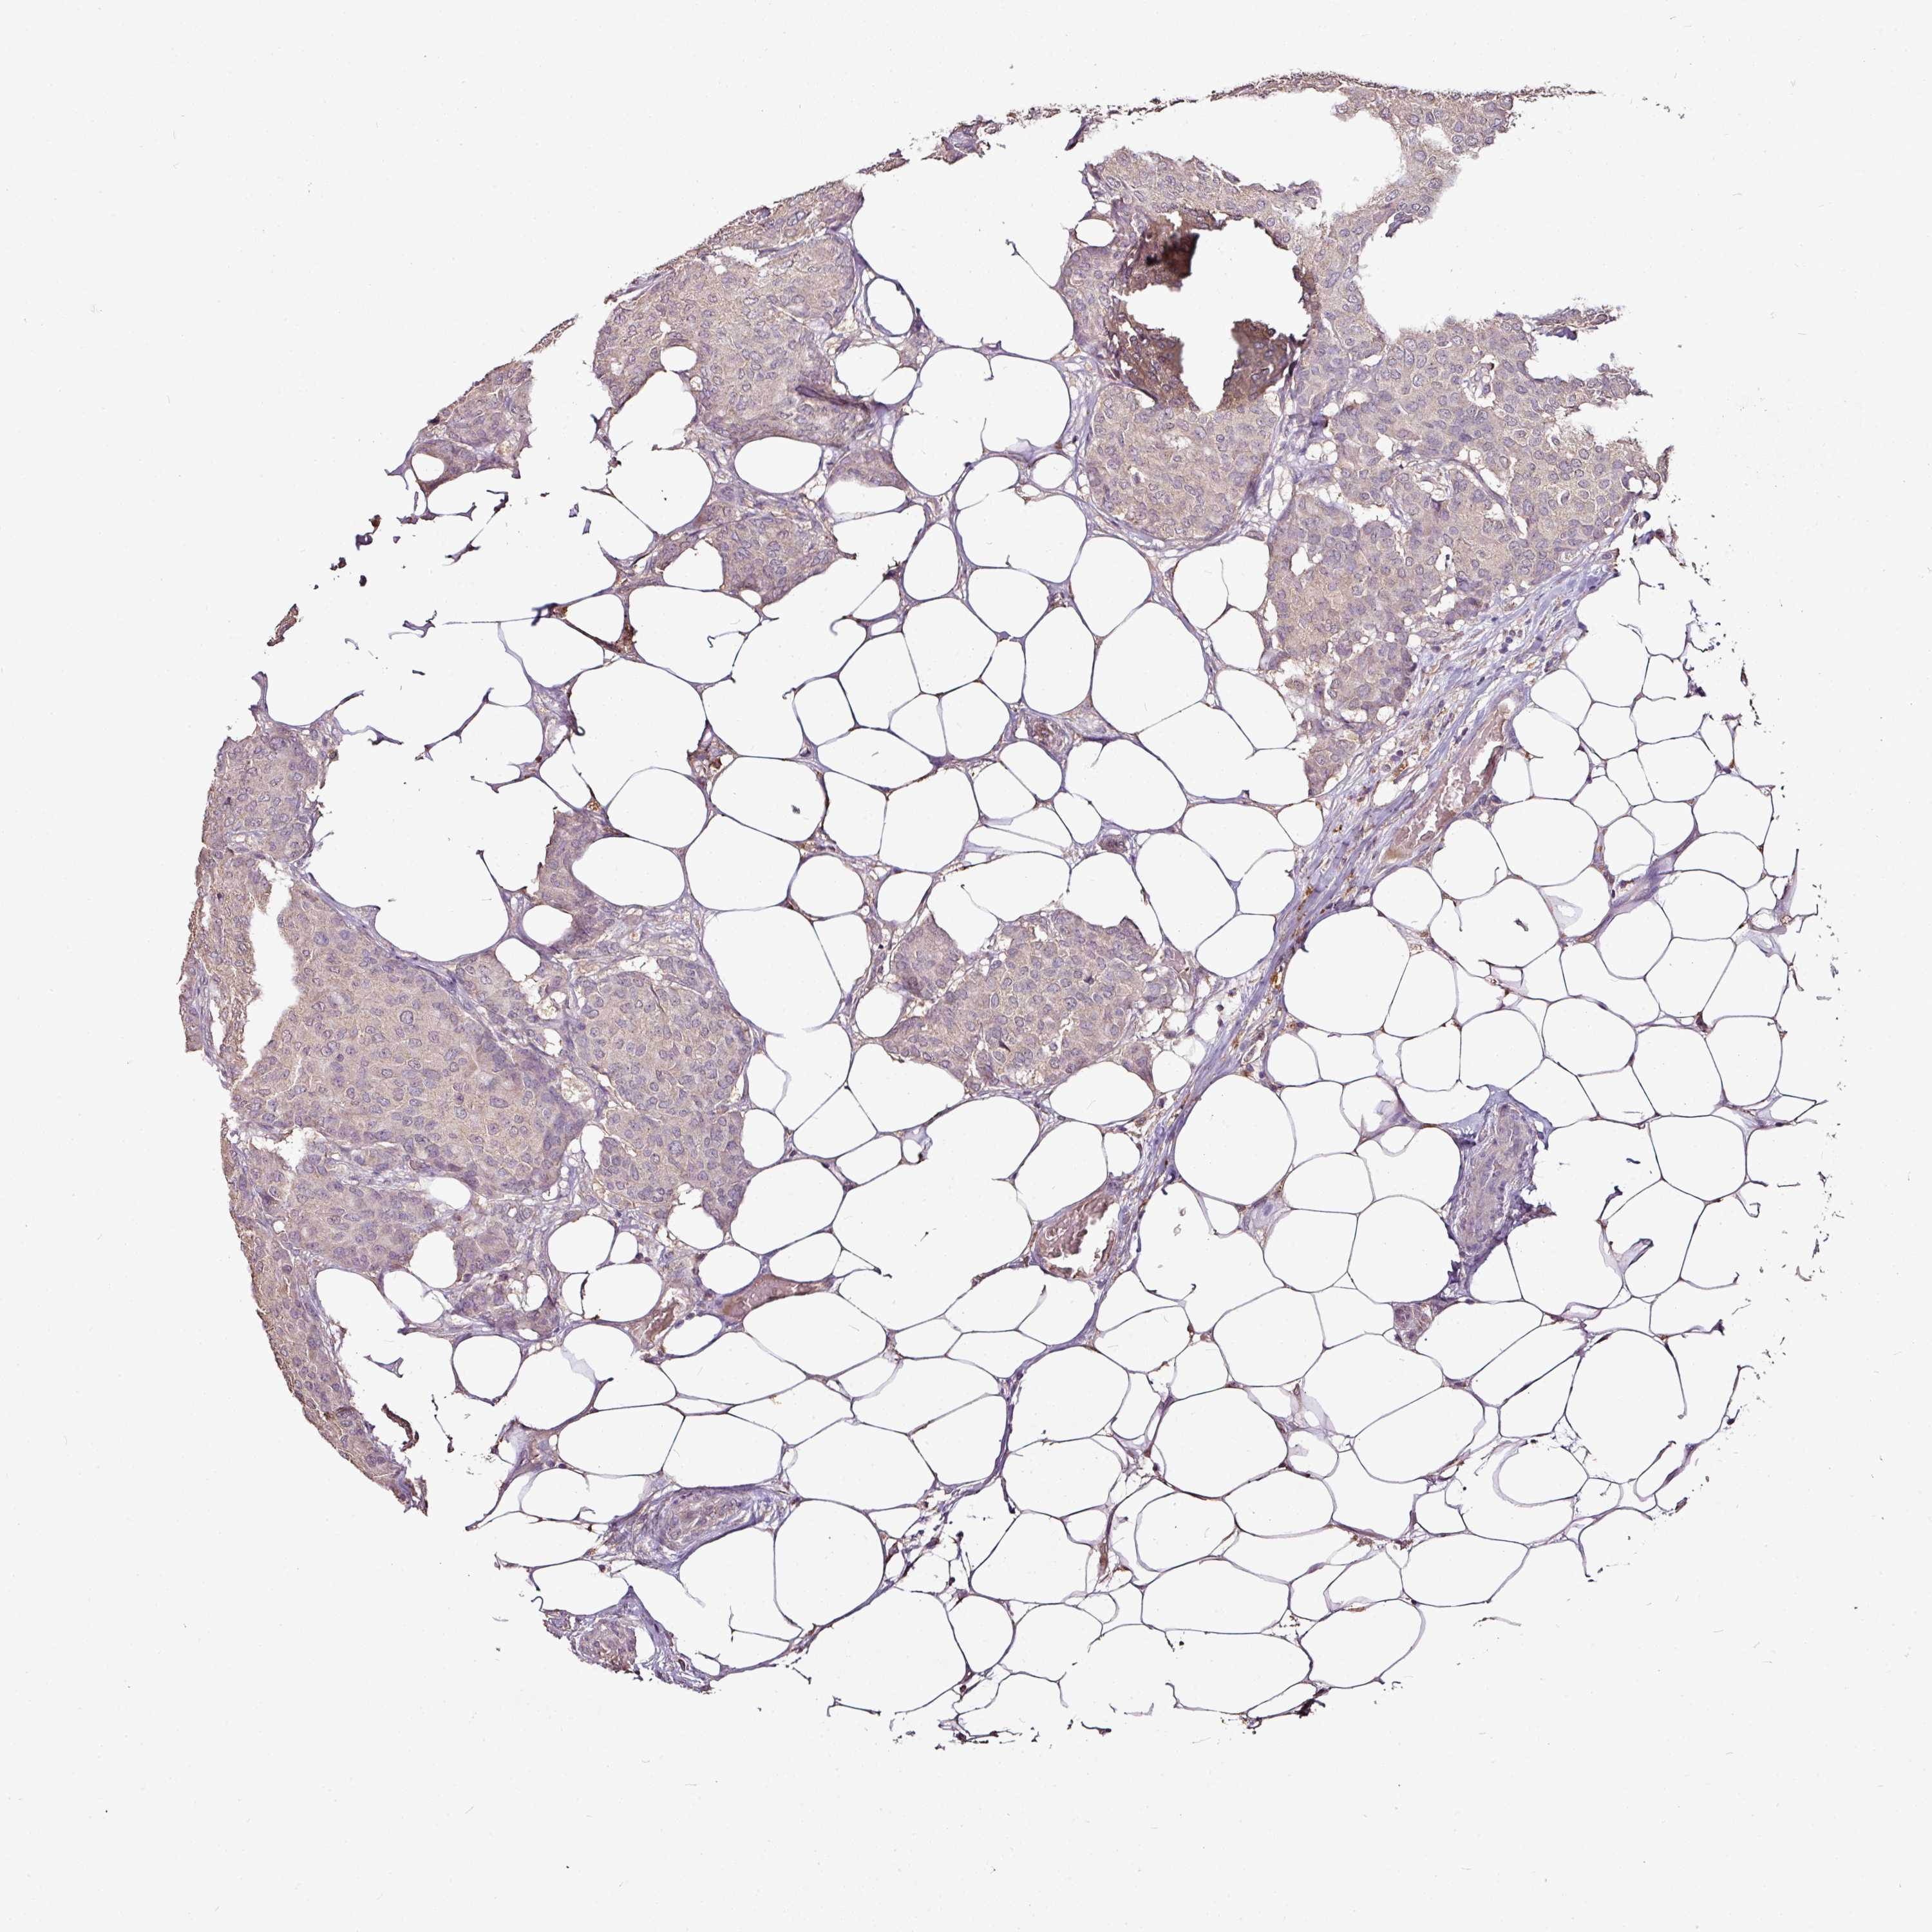

CANCER BREAST CANCER Show tissue menu

BRCA TCGA BRCA VALIDATION PROTEIN EXPRESSION

Breast cancer

Human cancer

Breast invasive carcinoma